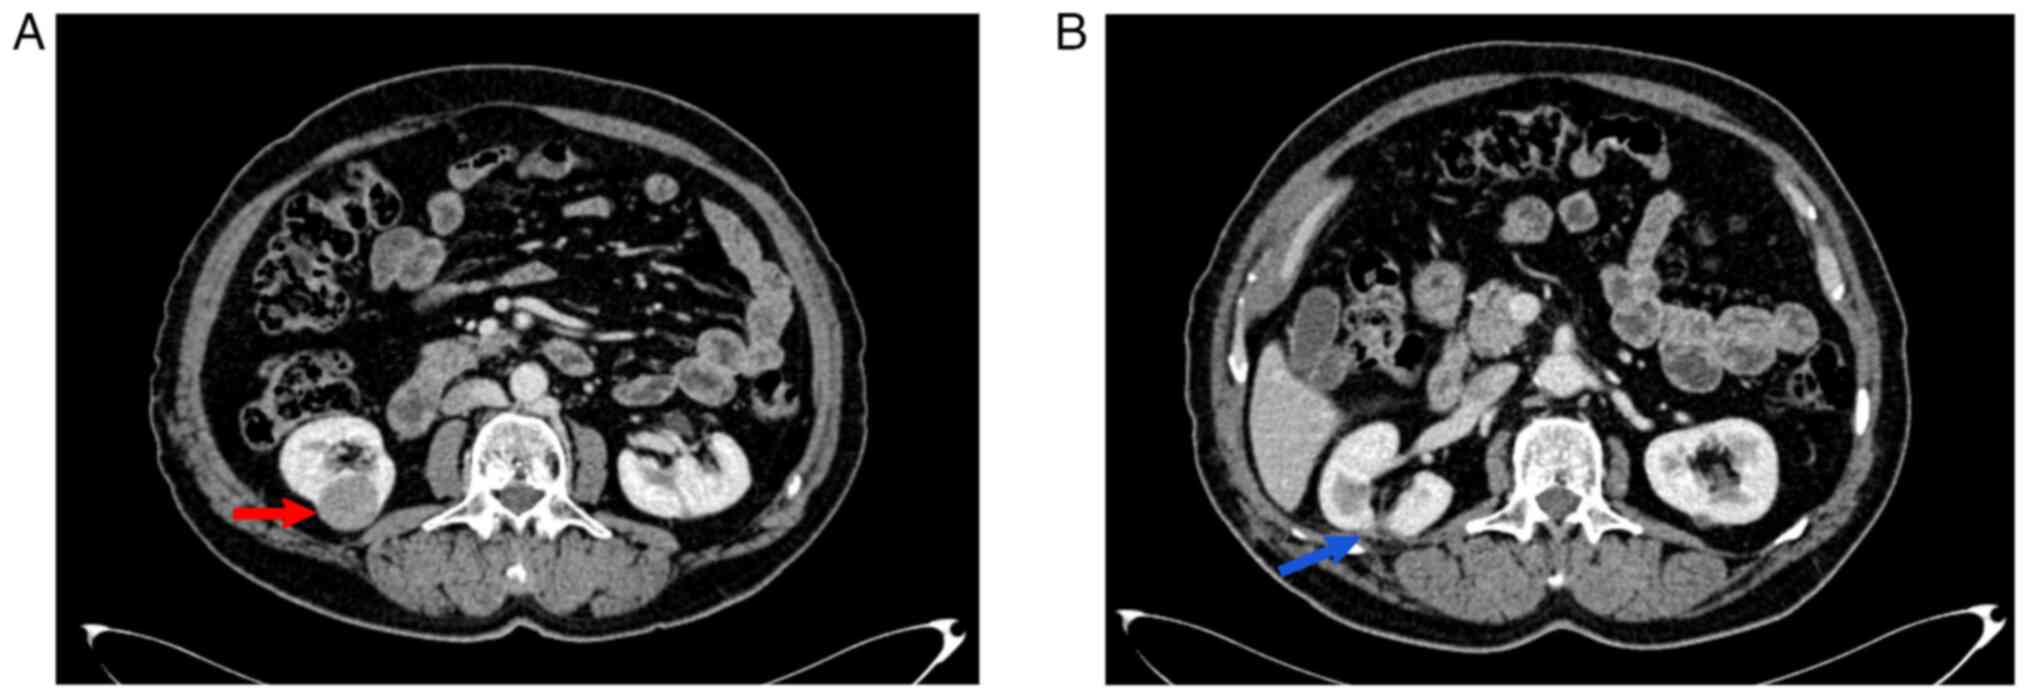

An abdominal ultrasound showcased a well-defined hypoechoic lesion, which measured 23x26 mm, found on the lateral aspect of the right kidney. A computed tomography (CT) scan of the chest, abdomen and pelvis with contrast material revealed evidence of a well-defined exophytic mass (3x3 cm) within the lower pole of the right kidney (it was stage T1a on the CT scan) (Fig. 1). The mass exhibited minimal enhancement at the arterial phase with more enhancement in the venous phase (equivocal enhancement) and no renal vascular invasion; the overall picture was suggestive of RCC. Under general anesthesia, the patient underwent a right partial nephrectomy, with the patient lying in the left lateral position, a right subcostal incision was made, and the kidney was found to be severely adhered to the surrounding peritoneum. All adhesions were released by the surgeon. Despite the CT scan indicating the mass in the lower pole, the mass was found to be located in the mid-pole of the right kidney intraoperatively. Bleeding was encountered due to a small parenchymal tear which was controlled and sutured. The renal pedicle was identified and bulldog forceps were placed. Following the partial nephrectomy of the mid-pole mass in the right kidney, positive margins were indicated in the intraoperative frozen section. This led the surgeon to further excise extra tissue from the base of the tumor in order for it to be sent for a histopathological evaluation. The warm ischemic time was measured and recorded as 12 min. Following excision, hemostasis was secured, a corrugate drain was placed and the wound was closed in layers. The resected mass had a gross appearance of a smooth capsular surface with a solid glistening grey color and few foci of necrosis. The mass had <1 cm of renal parenchyma on both of its lateral sides, although no parenchymal tissue was found centrally. The histopathological examination was performed at Anwar Shekha Medical City; the specimen was formalin-fixed and paraffin-embedded. The sections were cut using a microtome to a thickness of 4 µm and stained with conventional hematoxylin and eosin stain (MilliporeSigma). The procedure was performed at room temperature for 65 min using a Tissue-Tek Prisma Plus Automated slide stainer (Sakura Finetek Europe B.V.). The microscope used for examination was an Olympus BX-51 microscope with a camera adaptor (Olympus U-TV0.5XC-3) (Olympus Corporation) for obtaining images. The histopathological examination revealed the renal mass containing long tubules and a cord-like growth pattern of uniform, bland, and low cuboidal cells in an eosinophilic, focally vacuolated cytoplasm (Fig. 2). The stroma had myxoid foci and a bubbly appearance with extracellular mucin. A confirmed diagnosis of MTSCC was made with a pathological staging of T1aNxMx. The post-operative interval transpired without noteworthy incidents. Subsequently, a CT scan of the thoracic, abdominal and pelvic regions was conducted at 3 months post-operatively, indicating the absence of both recurrence and distant metastasis.

Figure 1

(A) Axial post-contrast image (arterial phase) from multidetector computed tomography illustrating a well-defined cystic tumor (red arrow) projecting from the lower portion-posterior aspect of the right kidney with heterogeneous enhancement of lower attenuation than the normal enhancing renal parenchyma. The tumor is confined within the Gerota fascia with a preserved fat plane between the lesion and right psoas muscle. (B) Post-contrast computed tomography scan demonstrates site of previous surgical scar (blue arrow) in the upper part of right kidney with fat stranding in the posterior perinephric region.